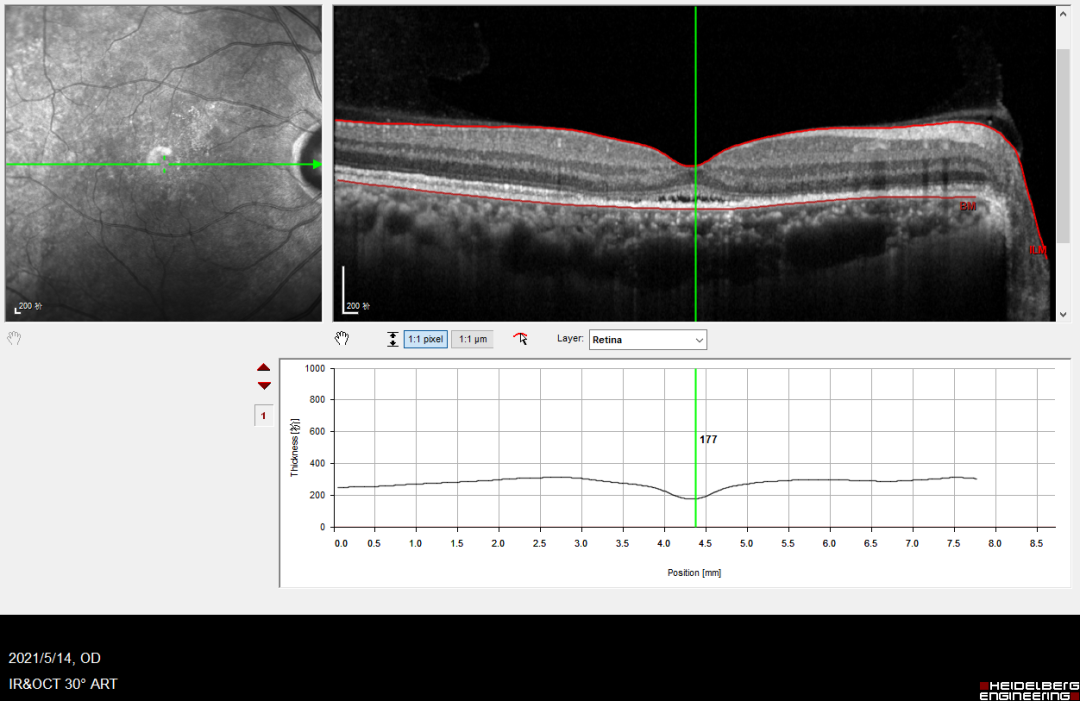

右眼视力1.0,OCT示水肿明显消退,中央黄斑厚度为177μm。未见明显激光斑。